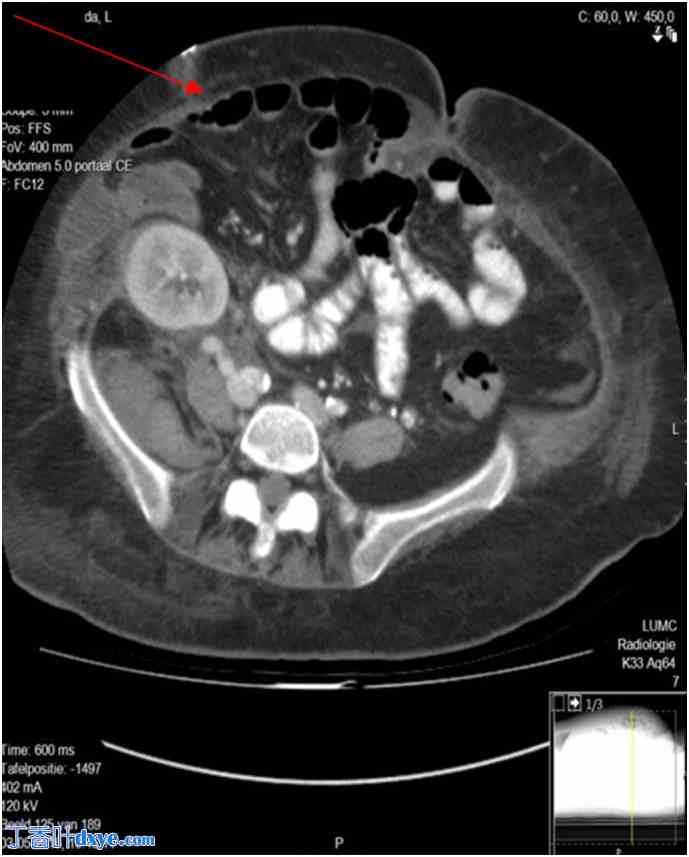

2016年12月,患者经先前的肾移植切口实施剖腹手术,修复腹壁上皮缺损(LIH)。修复前,患者进行了CT扫描,如图1所示。由于腹壁缺乏筋膜,传统的重建技术(例如腹腔镜腹腔镜重建术)无法实施。因此,患者选择了一块20 × 25 cm的生物网片(Strattice™)作为筋膜桥接,如图2所示。生物网片置于腹腔内,直接覆盖腹壁的大面积缺损。保留血管丰富的疝囊,并将其缝合于腹壁前表面,覆盖生物补片 (Strattice™),提供自然加固并确保完全覆盖。在疝囊和 Strattice™ 补片之间放置 Jackson-Pratt 引流管,以防止积液。

图 1.

腹部计算机断层扫描 (CT) 横切面,显示 LIH(红色箭头)。